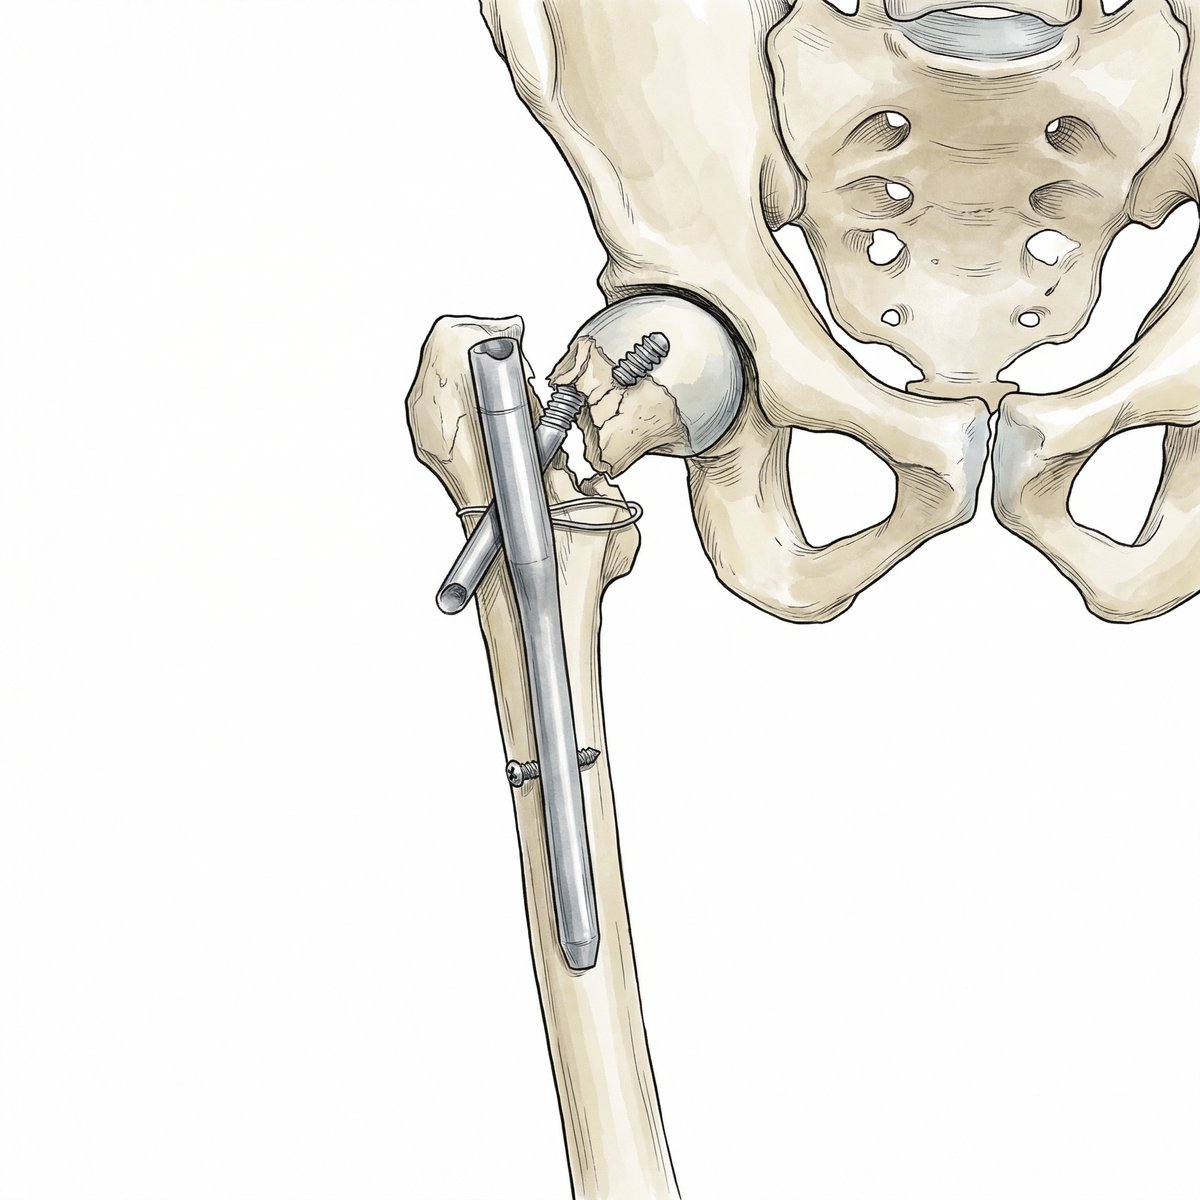

@traumaticum @ImprezowyKotek @orthobullets @orthotraumamd I see why a DHS… has the compression option that not all nails have, and it’s easier to add antirrotation or extra fixation screw in case needed. Also may let you correct valgus using the implant instead of forcing you to have it reduced before nail insertion. I like it.